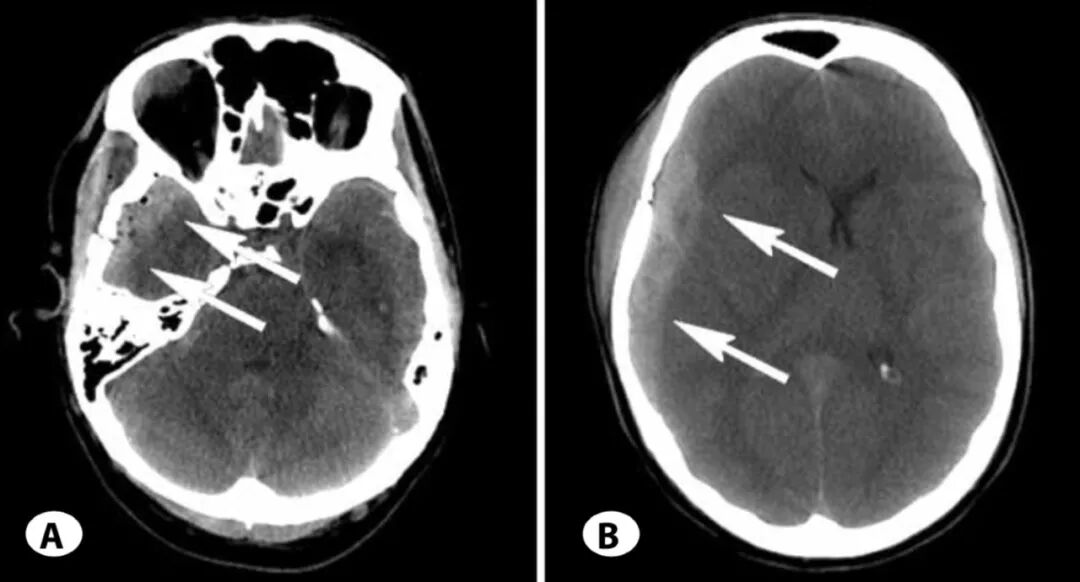

棘孔

脑血管解剖学习笔记第2期棘孔的解剖

6mm 棘孔是一短骨管,管长右侧 为7.3mm(6~14mm),左侧为 7.